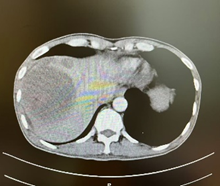

新辅助(两次HAIC和两个周期靶免治疗)后MR

由于病人一般情况较好,肝功能良好(Child-pugh A级),经多学科会诊临床确认肿瘤为IIb期肝细胞癌,属于可切除性肝癌,但存在高危复发因素,建议先行新辅助治疗后手术切除。经两次肝动脉关注化疗(HAIC)(奥沙利铂+5-Fu+亚叶酸钙方案)和两个周期的靶向免疫治疗(仑伐替尼+帕博利珠单抗方案),第二次介入造影是肿瘤血供不明显,第二次介入治疗4周后复查CT提示肿瘤缩小不明显但坏死征象明显,经MRI证实仍有少许血供,于是经多学科会诊后决定行前入路右半肝切除术。